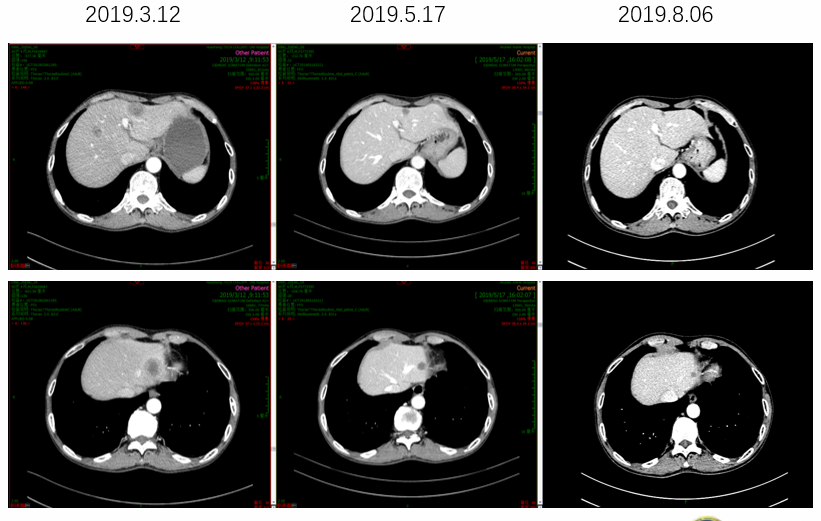

2019年3月胸腹部CT检查发现肝脏、肝门区淋巴结、肺内出现新发转移病灶。患者出现贫血,消瘦,纳差,白天卧床时间大于50%,PS评分3分。

image009.png

图3  一线治疗进展后胸腹部CT